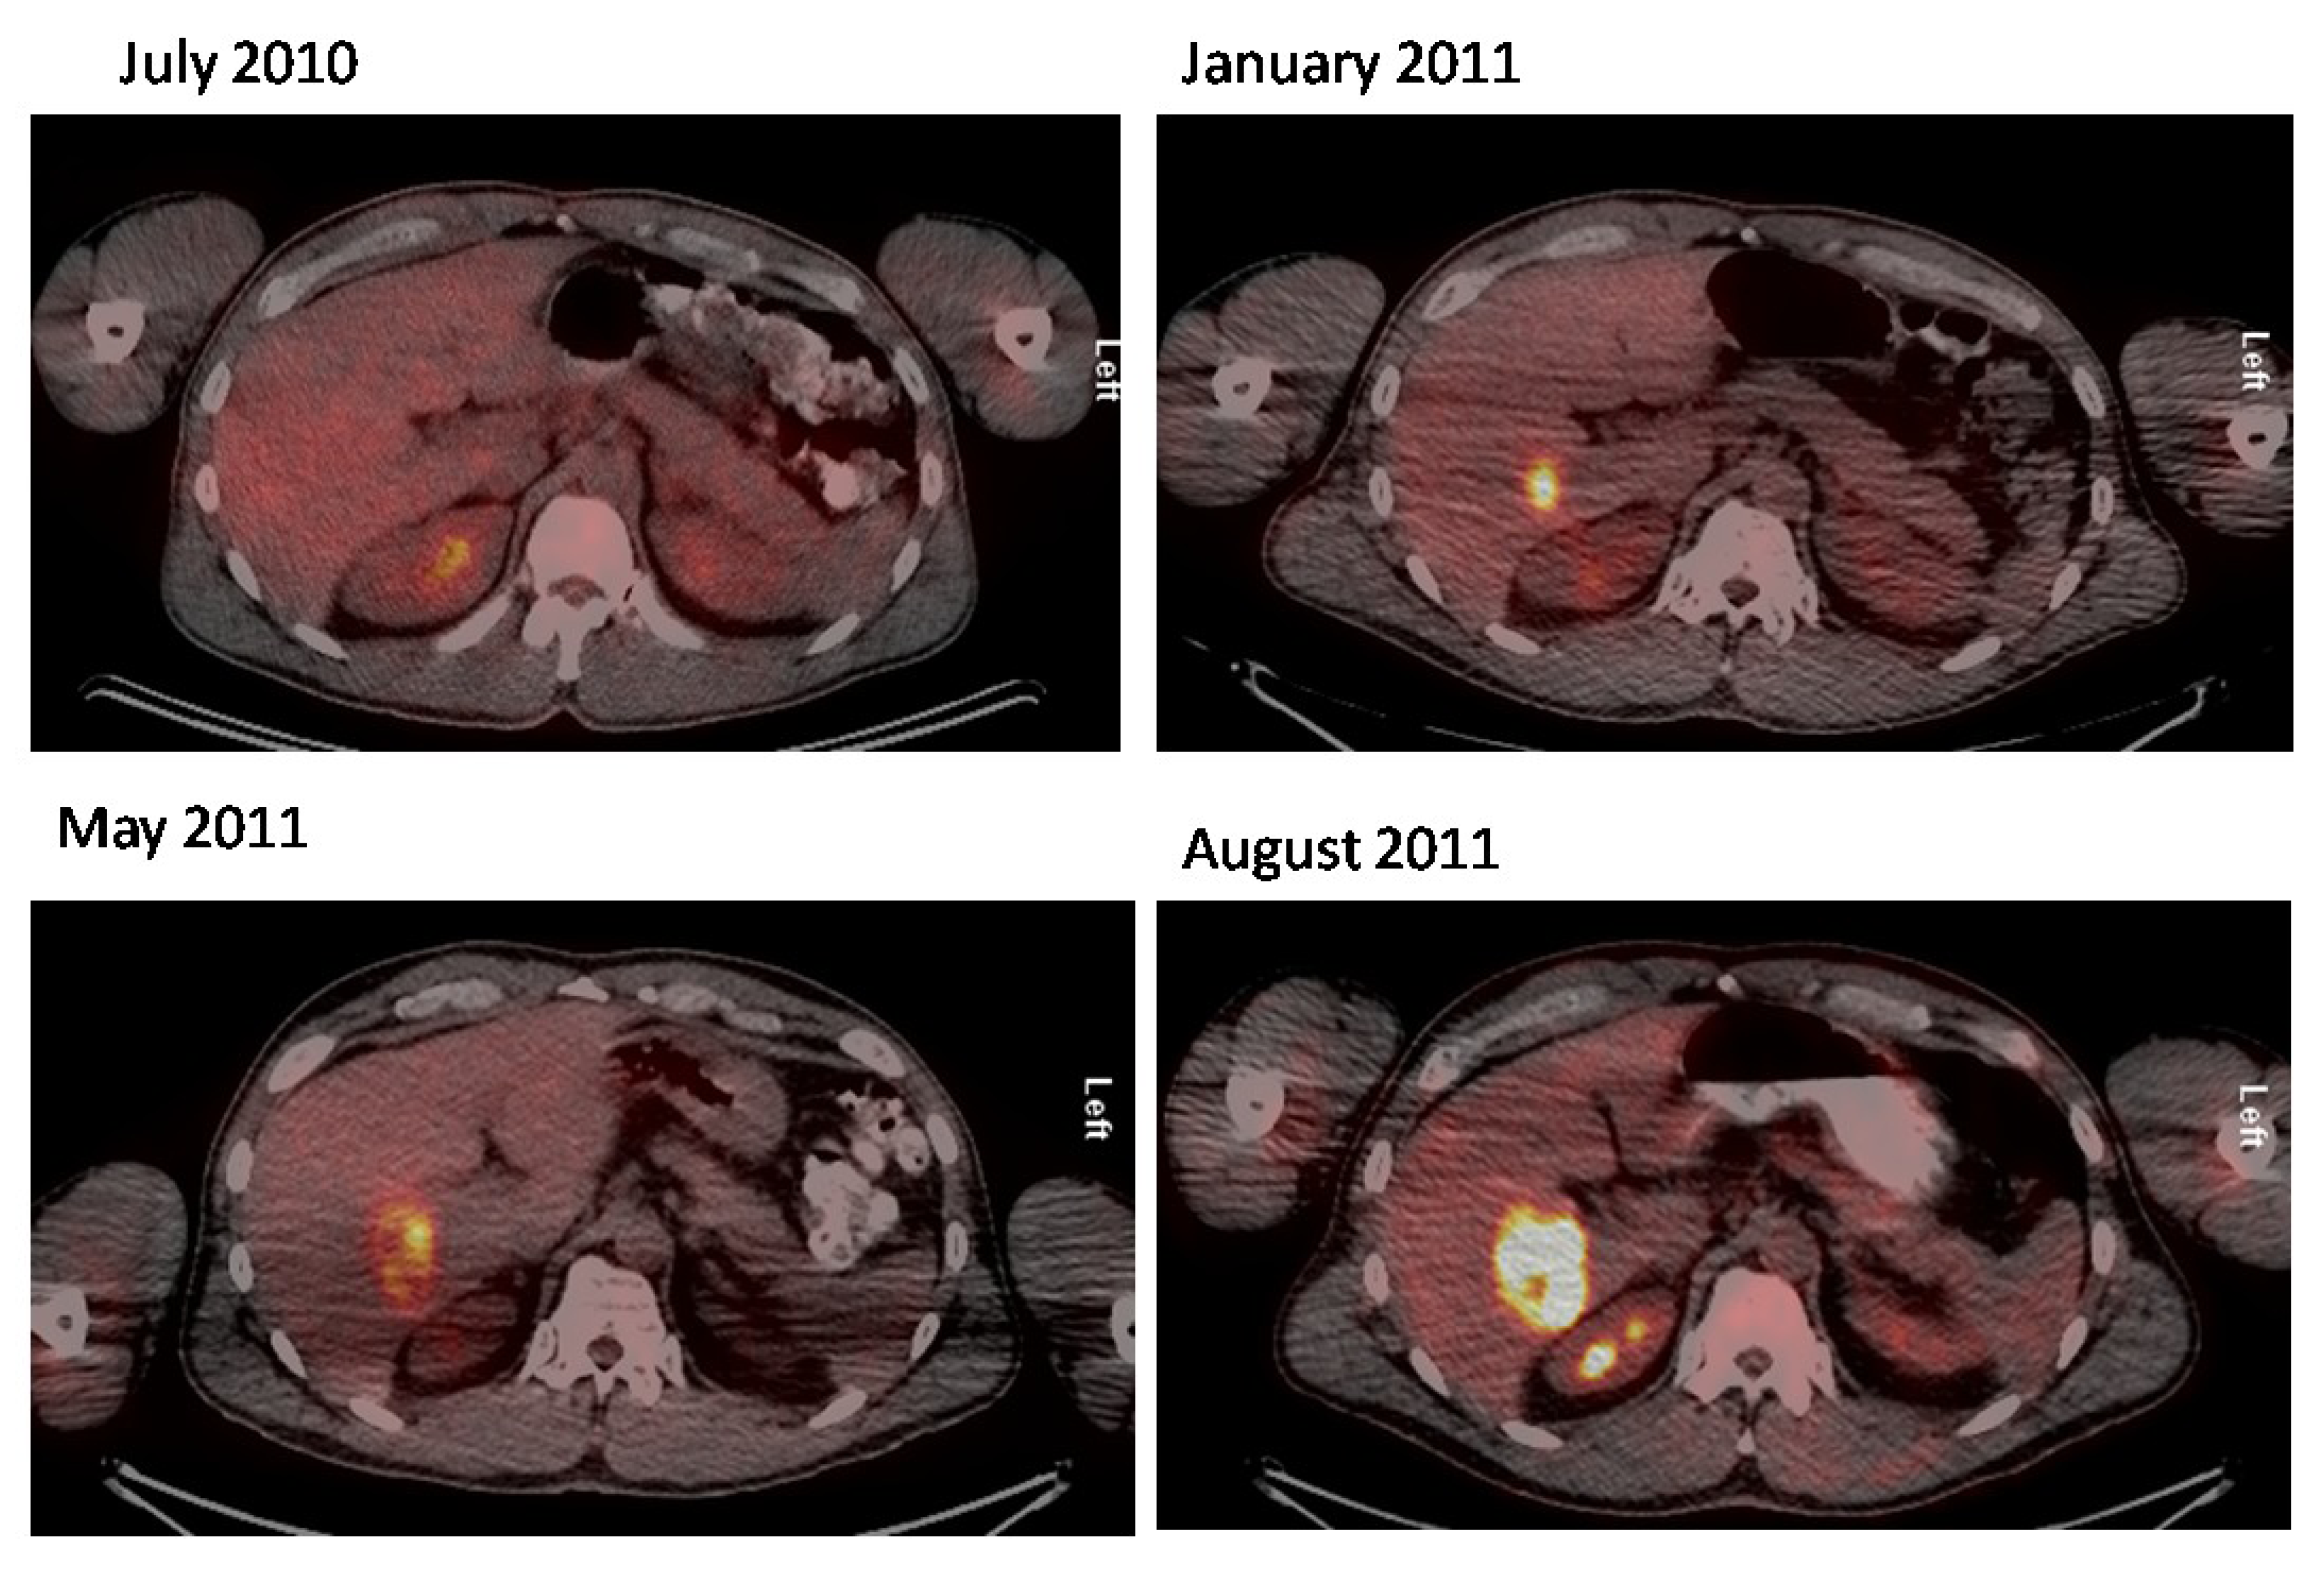

- Salavati, A.; Prasad, V.; Schneider, C.P.; Herbst, R.; Baum, R.P. Peptide receptor radionuclide therapy of Merkel cell carcinoma using (177)lutetium-labeled somatostatin analogs in combination with radiosensitizing chemotherapy: A potential novel treatment based on molecular pathology. Ann. Nucl. Med. 2012, 26, 365–369. [Google Scholar] [CrossRef]

- Schmidt, M.C.; Uhrhan, K.; Markiefka, B.; Hasselbring, L.; Schlaak, M.; Cremer, B.; Kunze, S.; Baum, R.P.; Dietlein, M. 68Ga-DOTATATE PET-CT followed by peptide receptor radiotherapy in combination with capecitabine in two patients with Merkel cell carcinoma. Int. J. Clin. Exp. Med. 2012, 5, 363–366. [Google Scholar]